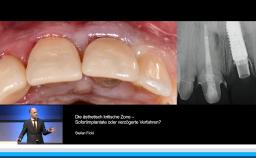

Implantatverlust mit Defektsituation: Erneute Implantation oder Alternativtherapie?

Basierend auf diversen Studien und eigener klinischer Erfahrung stellt Dieter Weingart seine Erkenntnisse und Schlussfolgerungen zum Thema Implantatverlust mit Defektbildung vor. Er illustriert das Thema mit eigenen klinischen Fällen inklusive Langzeit-follow-ups.

• die Empfehlung einer erneuten implantologischen Versorgung nach Implantatverlust mit Defektbildung diskutieren können

• Erfolgs- und Risikofaktoren einer erneuten Implantation benennen können